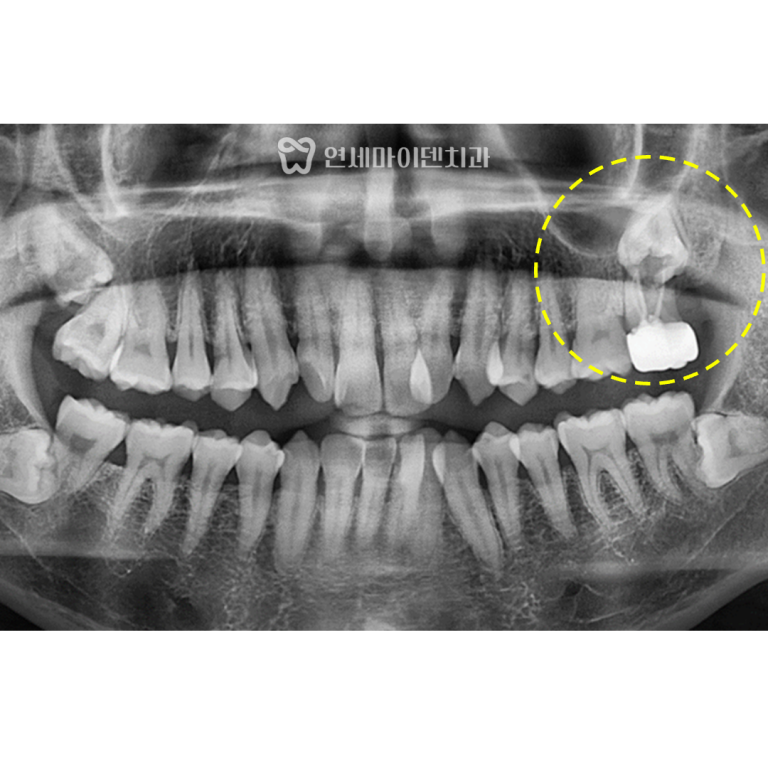

반대편 어금니(#46)는

스플린트 크라운으로 수복되어 있었습니다.

겉으로 보기엔 멀쩡했지만,

내부에는 깊은 충치가 진행돼 있었습니다.

보철물을 제거하자 치아 내부 조직이 심하게 손상되어 있었고,

결국 보존 불가로 판단했습니다.

이에 따라 발치 후 즉시 임플란트를 진행했습니다.

다행히 치조골 상태가 양호해 즉시 식립이 가능했습니다.

임플란트 식립 후 골이식과 멤브레인 적용을 통해 뼈의 안정화를 유도했고,

2주 뒤 봉합사 제거 후 출국하실 수 있도록 계획했습니다.

최종 보철물은 귀국 시기에 맞춰 맞춤 제작하여 완성했습니다.

💡 스플린트 크라운(여러 치아가 묶인 형태)은

청결 관리가 어렵고, 내부 충치가 생겨도 확인이 늦을 수 있습니다.

이후에는 단독형 크라운으로 교체하여 관리 효율을 높였습니다.